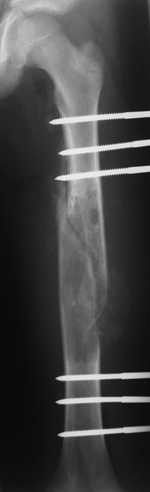

Re: Pathological fracture femur

Most likely fibrous dysplasia, we had the same case but younger age patient 4 years ago treated by uniplanar ext fix followed by percut. curretage and bone marrow injection and healed well.

at this age IMN can solve the problem .